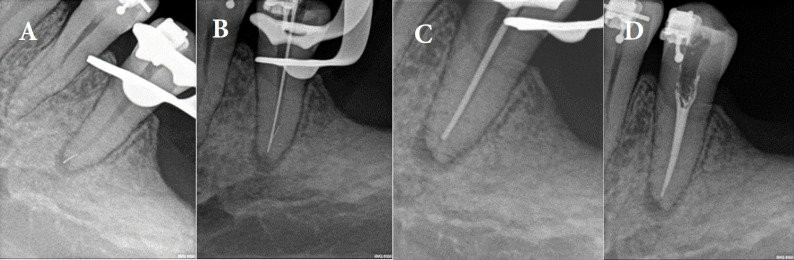

感觉异常被描述为由神经损伤引起的灼烧或刺痛感或部分麻木。感觉丧失可能是可逆性和/或不可逆性神经损伤的结果,可由局部或全身因素引起。局部因素包括埋伏牙造成的外伤性损伤、局部注射、牙髓治疗、种植体放置和接触有毒物质。本文报告一例麻醉注射后的感觉异常。一名44岁男子报告咀嚼和受寒时有中度疼痛。经临床检查,牙断裂线延伸在下颌左第二前磨牙冠中远端,用16倍显微镜观察。诊断为牙裂综合征,行根管治疗。第一次预约后,患者报告左侧下颌骨感觉改变,麻木和电击感,因此被诊断为精神神经感觉异常。双氯芬酸钠、硫胺素、氰钴胺、吡哆醇治疗7天,完成根管治疗和修复治疗。随访时间分别为1、3、6、8个月。第一个月后,感觉异常的感觉仍然存在,病人正在经历痛苦的“电击”。在8个月的随访中,感觉异常消失,感觉恢复正常。

Paresthesia is described as a burning or prickling sensation or partial numbness caused by neurologic injury. The sensory loss may be the result of a reversible and/or irreversible nerve damage, and it can be caused by local or systemic factors. Local factors include traumatic injuries caused by impacted teeth, local injection, endodontic therapy, implant placement and exposure to toxic materials. This article reports a paresthesia by anesthetic injection. A 44-year-old man reported moderate pain during chewing and exposure to cold. Upon clinical examination, extension of the tooth fracture line was in the mesiodistal region of the mandibular left second premolar crown and was detected with 16× magnification of microscope. The diagnosis was cracked tooth syndrome, and root canal treatment was indicated. After the first appointment the patient reported altered sensation on left side of mandible, numbness and electric shock sensation, and therefore was diagnosed with mental nerve paresthesia. Diclofenac sodium, thiamine, cyanocobalamin, and pyridoxine were prescribed for 7 days as part of the treatment, and then root canal and restorative treatments were completed. Patient was scheduled for follow-up appointments after 1, 3, 6, and 8 months. After the first month, the feeling of paresthesia was still present and the patient was experiencing a painful "electric shock". At the 8-month follow-up visit, the paresthesia had been resolved with return of normal sensation.